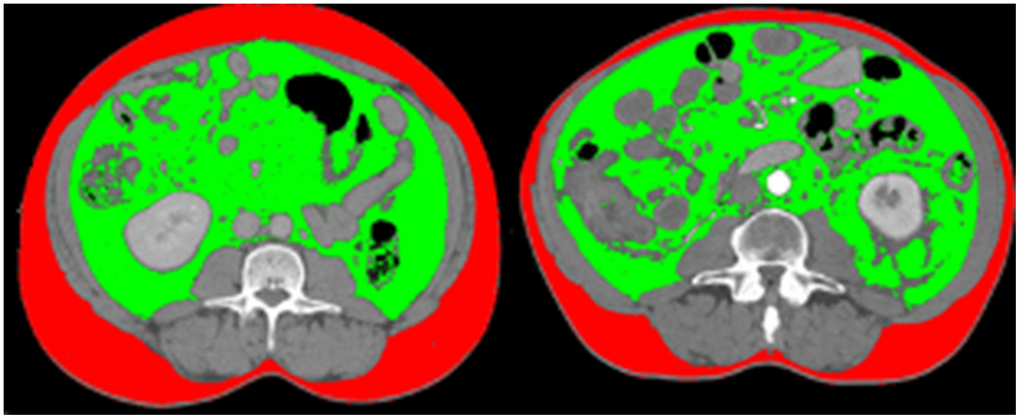

From July 2016 to January 2019, a total of 140 IBD patients were recruited. Characteristics of the IBD patients are shown in Table 1. The prevalence of visceral obesity was 38% for IBD patients (57 out of 150 patients), with 51% (37 out of 72) for CD patients and 26% for UC patients (20 out of 78 patients) respectively. The comparison of visceral obesity with non-visceral obesity patients with different BMI was illustrated in Figure 1 using sliceOmatic. In Figure 1, the first patient has lower BMI than the other patient, and its VAT/SAT ratio is also lower, which means that patient with lower BMI has less visceral obesity. The median age of our patients is 41 years old, with range of 22 to 68 years old. Females take a larger portion than males (72% vs. 28%). 72 patients were diagnosed with CD and 68 patients were diagnosed with UC. Patients had an average history of IBD for 7 years. 47% of these IBD patients admitted chronic constipation at recruitment. 23% of them had a history of treated anxiety or depression (Table 1). We analyzed the differences of disease duration, severity/category, and treatment between the visceral obesity group and non-visceral obesity group and found no statistical difference in these two groups (P > 0.05).

Figure 1. Comparison of visceral obesity of two patients with same BMI. The first patient has lower BMI than the other patient (20.1 kg/m2 vs. 29.3kg/m2), and its VAT/SAT ratio is also lower, which means that patient with lower BMI has less visceral obesity (VAT/SAT ratio: 1.22 vs. 2.48).